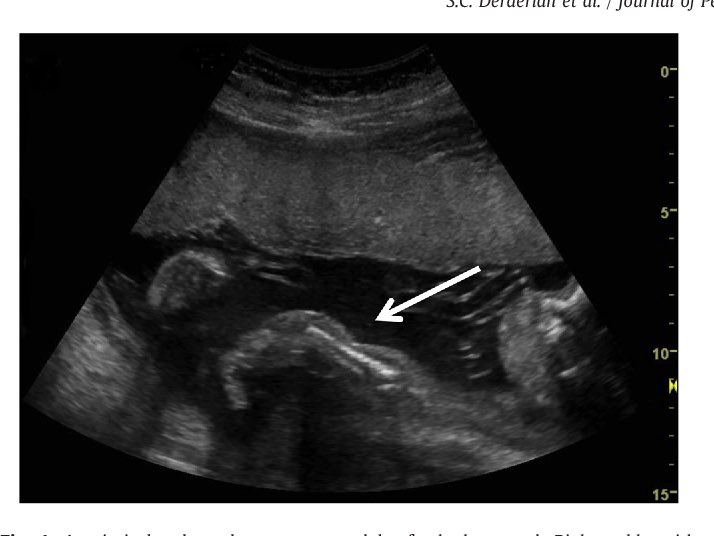

بنعرف المرض : هو عباره عن قطع جزئي او كلي يجي بالكيس من غلافه الداخلي !! اي كيس طيب ؟ الي يغطي الجنين داخل رحم الام حلو ! ، ويكون جدائل او زي السلك يلتف على بعض الاطراف ويقطعها ، سواء الاصابع او الاطراف كامله وغالبا ماشوفه بالاصابع طبعا الغلاف الخارجي مايكون فيه اي مشكله.

طبعا تختلف شدته من حاله الى اخرى بعضها يجي بتر باصابع القدم ، او اصابع اليد ، بعضها تكون الاصابع ملتصقه ببعض او مبعده وهذي تنحل جراحيا وله اكثر من جراحه ، صحح وممكن

ممكن يسبب تشوهات وامراض ثانيه مثل ال (clubbed foot) او ممكن يتسبب في بتر كامل للLimps ! ، وممكن بعد ان اللف يجي على الراس او الحبل السري ويؤدي لوفاة الجنين ??